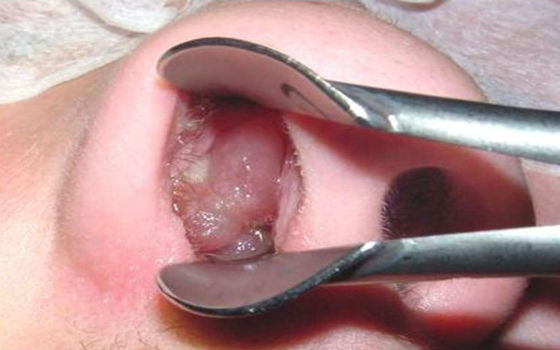

Как выявить увеличенные аденоиды у ребёнка и к кому обратиться за помощью? Только ЛОР-специалист может поставить этот диагноз после специального осмотра. При обычном осмотре горла педиатр не может обнаружить признаки патологии, однако опытный врач-педиатр может предположить, что у ребёнка увеличены аденоиды, основываясь на перечисленных родителями симптомах и частых заболеваниях органов респираторной системы. В таком случае педиатр направляет ребенка на консультацию к ЛОР-врачу, где проводится осмотр при помощи медицинских инструментов.

В настоящее время осмотр с применением зеркал считается наиболее рекомендуемым, поскольку применение пальцевого осмотра, которое ранее широко использовалось, может вызывать у детей тошноту. Рентгеновское исследование при диагностике аденоидов было признано малоэффективным из-за частого искажения результатов.